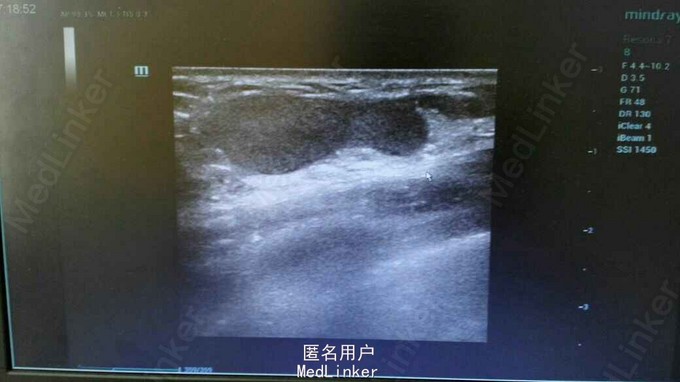

女性,25岁,发现右乳肿物2周。2周前无意中发现右乳肿物,不规则状,约3*2.5cm,无疼痛,无红肿,无乳头溢乳,与月经周期无明显相关。既往体健。

右乳9点钟方向,距离乳头5cm可扪及一肿物,不规则状,约3*2.5cm,质中,边界欠清,按压有轻微疼痛,活动度一般,挤压双侧乳头无液体流出。双侧腋窝LP(—)。我院乳腺彩超示:右乳实性肿物,BI—RADS—3类,(乳腺纤维瘤?)。